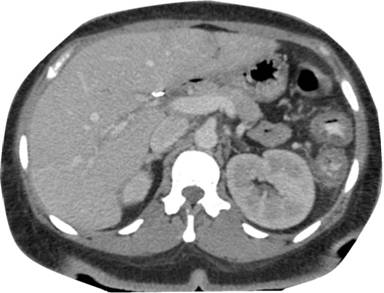

Although the patient had been infected with HIV for two years, she was never on antiretroviral therapy. Her vision in both eyes was also diminished with near total blindness of the left eye. She was a non-smoker and denied alcohol use. Her past surgical history was significant for cholecystectomy. In the emergency department, she was febrile (101.4°F; 38.6°C) and tachycardic (heart rate: 139 beats/min). Chest X-ray was normal, but computed tomography (CT) scan of the abdomen showed non-specific pancolitis with no sign of acute pancreatitis (Figure 1). Her serum amylase and lipase were normal.

Figure 1. CT scan of the abdomen in our patient two weeks before developing acute pancreatitis. |